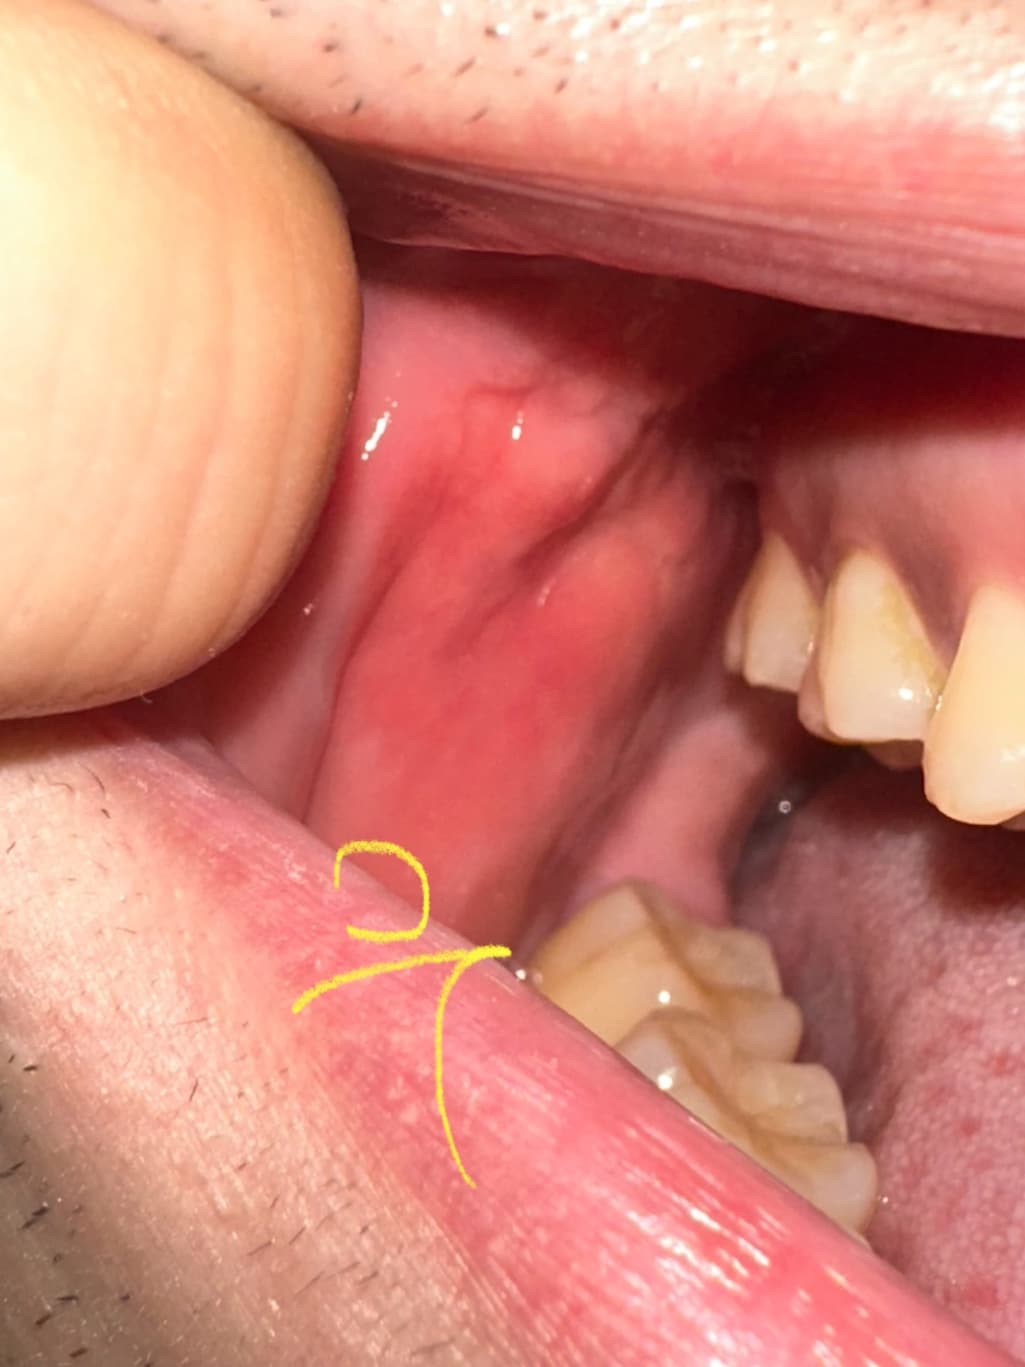

구강내 우측 상당 어금니 부분 옆 볼살에 이질감이 느껴집니다

안냥하세요 평소에도 좌측과 우측 동일하게 혹 비스무리흔디 잡히고 그랬었습니다 다만, 이틀 전 부터 우측 부분이 붓고 평소보다 살짝 더 심하게 느껴지는 것 같았슺니드 이게 정살일가료? 참고로 흡연 11년 하루 8개이며 나으ㅡㅡㅡㄷ

• 2번 째 사진